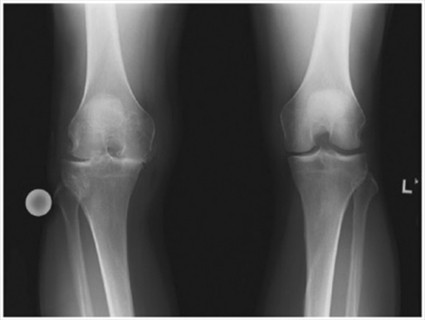

Current medicinal treatments for knee osteoarthritis (OA) do not modify the disease course. A major barrier to the development of disease-modifying interventions is the nature of knee OA progression, where initial articular cartilage damage triggers a vicious cycle of molecular events and tissue interactions in a downward spiral and rapidly progresses to diffuse knee OA. Stopping this elaborate process is a challenge, making preservation and restoration of articular cartilage a critical topic of investigation.

Early detection to block disease progression

Identification of patients with knee OA symptoms who lack joint degeneration would provide opportunities to intervene prior to the development of severe disease with discernable structural changes. The first step of such treatment could be to invoke an anti-catabolic response to prevent further cartilage degradation. The second step would be the application of an agent to promote cartilage regeneration. However, this two-step approach is unlikely with a single small molecule.

Cartilage defects can be repaired effectively in early stages. However, the field of matrix-based therapies and engineered cartilage is unlikely to reach the point of slowing disease progression without reliable biomarkers to identify OA at earlier stages.